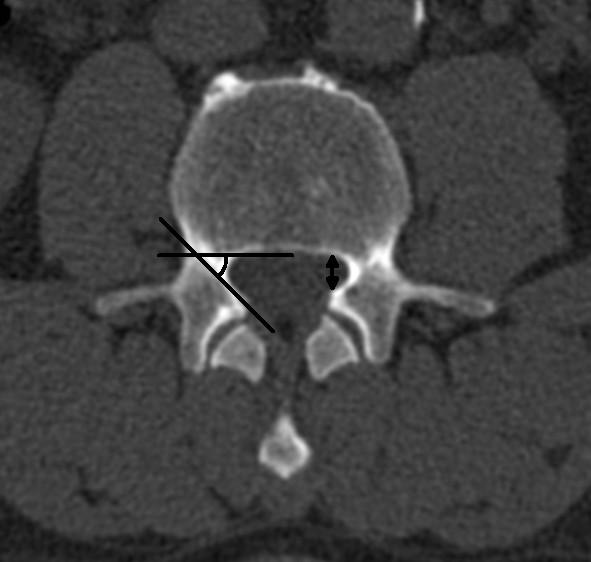

25 studies reporting on radiological signs of LSS and four systematic reviews related to the evaluation of different treatments were found. Ten different parameters were identified to quantify lumbar spinal stenosis. Most often reported measures for central stenosis were antero-posterior diameter (< 10 mm) and cross-sectional area (< 70 mm(2)) of spinal canal. For lateral stenosis height and depth of the lateral recess, and for foraminal stenosis the foraminal diameter were typically used. Only four of 63 primary studies included in the systematic reviews reported on quantitative measures for defining inclusion criteria of patients in prognostic studies.

发现 25 篇报告 LSS 影像学征象的研究和 4 篇与评估不同治疗方法相关的系统评价。确定了 10 个不同的参数来量化腰椎椎管狭窄症。最常报道的中央狭窄测量值为椎管前后径(<10mm)和横截面积(<70mm²)。对于侧方狭窄,通常使用侧隐窝的高度和深度以及椎间孔狭窄的椎间孔直径。在纳入系统评价的 63 项主要研究中,仅有 4 项报告了用于确定预后研究患者纳入标准的定量测量值。